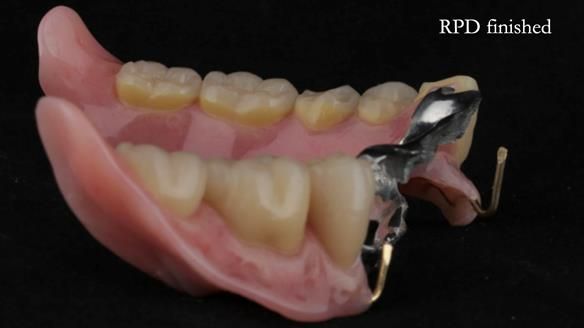

Instead, we made a Scandinavian-style, metal-based lower RPD.

It’s worth saying that the lower denture in this case was made in the early days of Rowan and me using the Scandinavian approach. Rowan cast the metalwork himself for this denture.

Looking back, we would make this denture more hygienic now. The design and finish would be more refined and delicate, particularly when compared with the upper metalwork, which was made later using Chris Hesketh’s chrome work. I will discuss this in detail at the study club.

That said, the lower denture worked beautifully. It did exactly what it was meant to do, even though, by today’s standards, it looks a little agricultural.